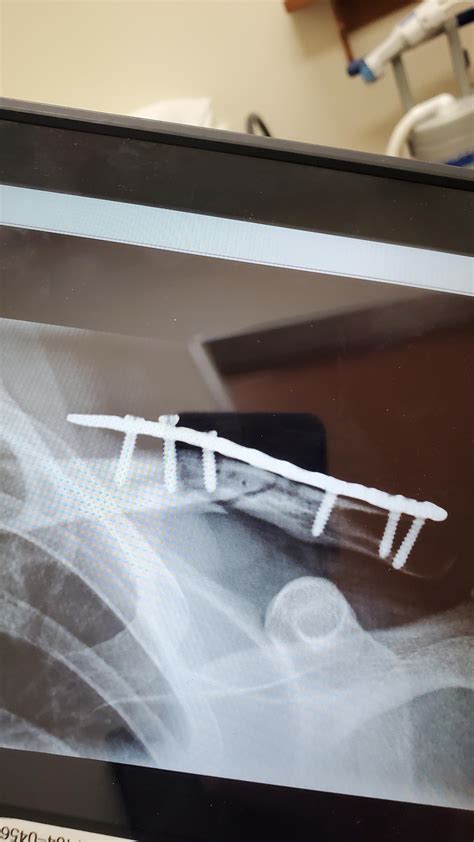

Collarbone pain at sternum : DiagnoseMe

Collarbone pain at sternum : DiagnoseMe